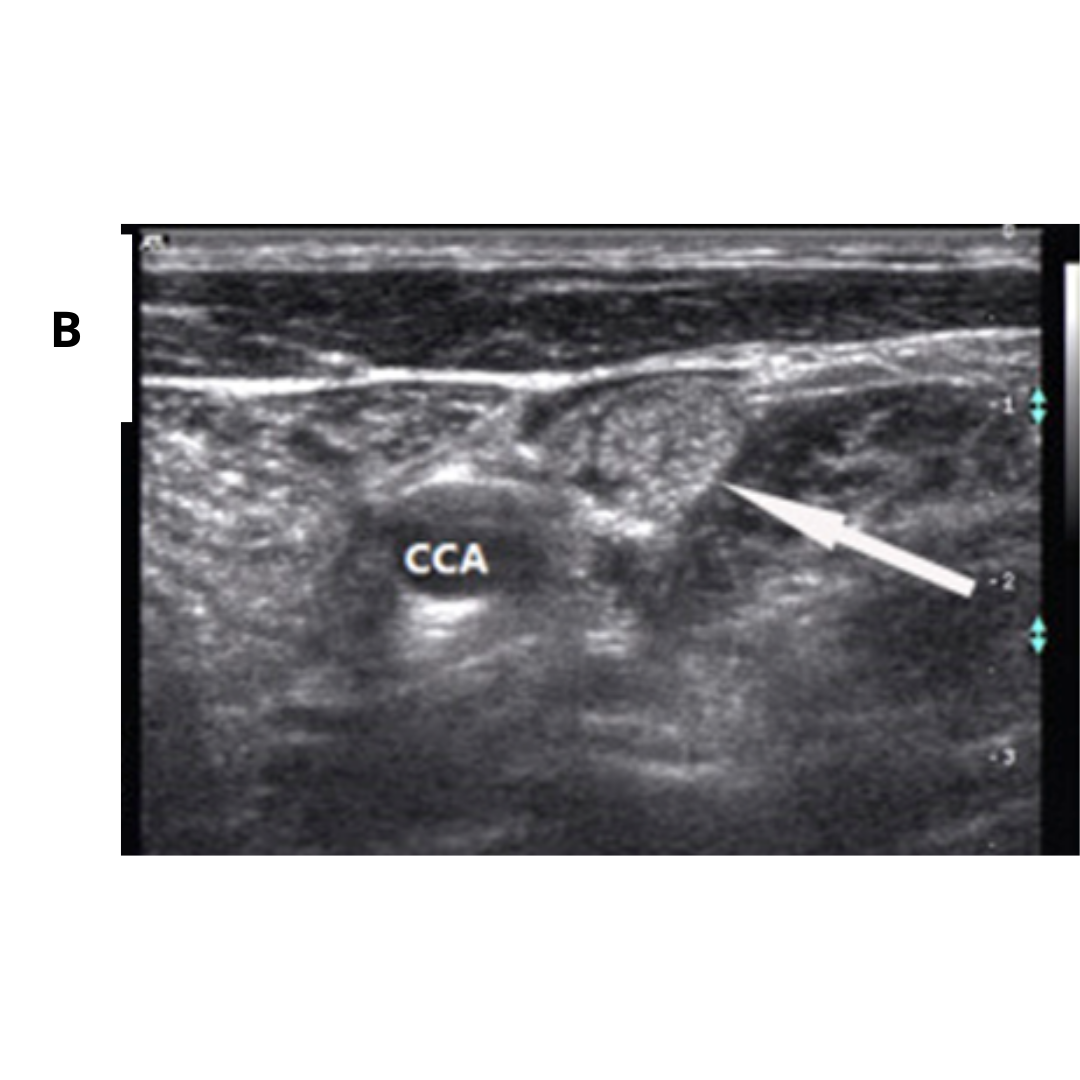

En ambas presentaciones existirá un alto porcentaje de visualización de ganglios cervicales aumentados de tamaño, con MCC difusas, similares a las que se presentan en el parénquima tiroideo.

Fig2. A) Masa hipoecoica mal definida, con microcalcificaciones difusas y dispersas que ocupaban toda la glándula. B) Ganglio linfático cervical aumentado de tamaño con múltiples microcalcificaciones dispersas (2).

Fig4. (A) En lóbulo tiroideo derecho, 1/3 medio, se visualiza nódulo sólido, hipoecogénico, mal delimitado con múltiples calcificaciones puntiformes en su interior (cuerpos de Psamoma). (B) Estas también se presentan de manera difusa periféricas al nódulo. (C) En Región cervical derecha, GIV, se visualiza ganglio cervical aumentado de tamaño, con múltiples imágenes puntiformes hiperecogénicos en su periferia e interior sugerente de microcalcifcaciones.